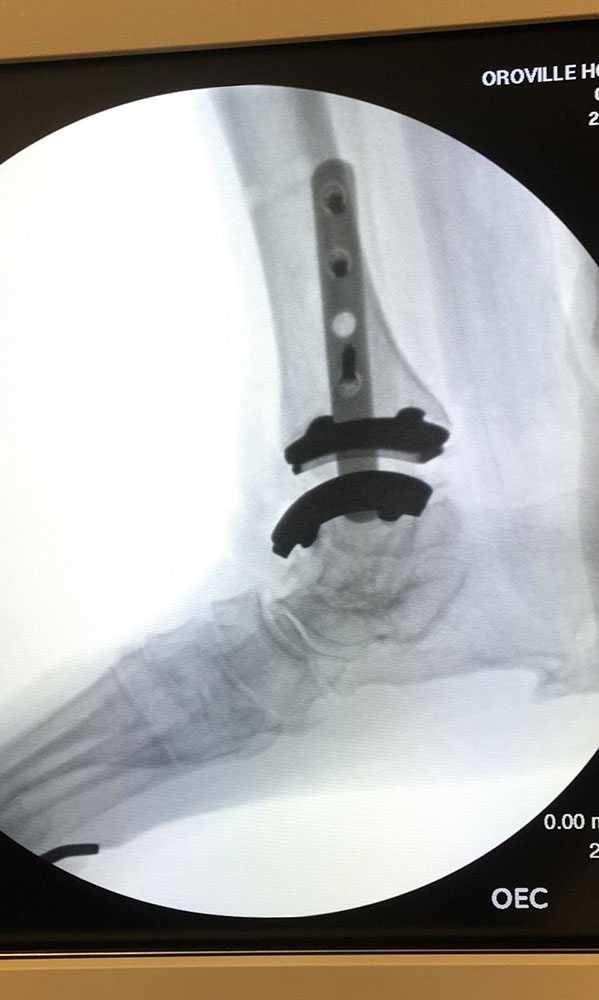

"Surgical misadventure" by another surgeon about 8 years ago. The wrong fixation was used for a flatfoot repair, & the deformity was not corrected. Patient came in with severe foot & ankle pain, with no arch at all. She was unable to play with her grandchild because the pain was so bad, & because she felt unsteady. The old hardware was removed, a lateral calcaneal lengthening osteotomy was performed along with a medial column/1st ray realignment. The ankle was painfully arthritic, & patient elected a total ankle replacement vs. an ankle fusion. She is now able to walk pain free & play with her grandchildren!